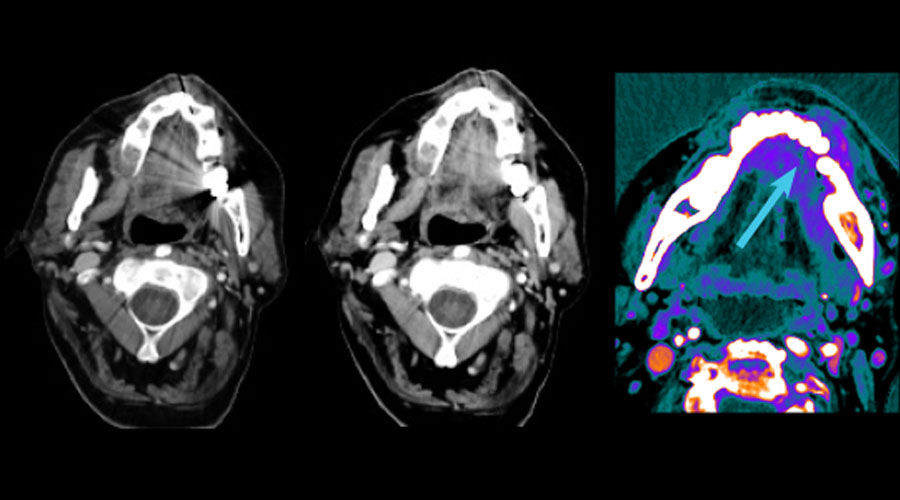

GSI MAR

Left: 40 keV; Right: 40 keV with GSI MAR. GSI Metal Artifact Reduction (GSI MAR) is a dual energy metal artifact reduction algorithm designed to reveal anatomic details obscured by metal artifacts. GSI MAR benefits for radiation oncology: reduced artifacts for more productive target delineation and dose calculation.